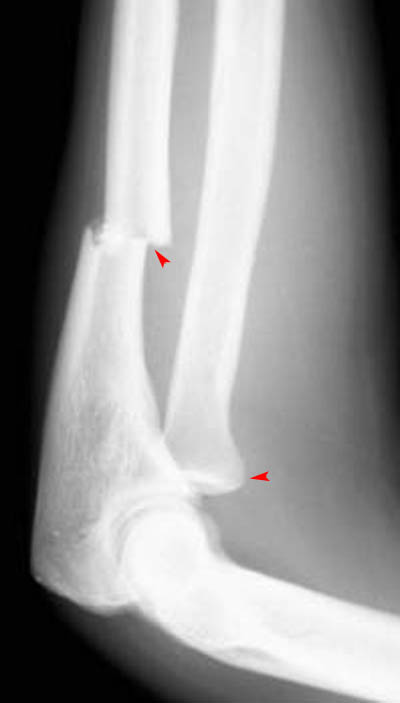

11) What abnormalities of the elbow can be observed in the image below?

The arrows on the image above indicate an Ulnar Fracture and Radial Head Dislocation.

12) Based on your findings, what fracture is shown in the above image? Monteggia Fracture